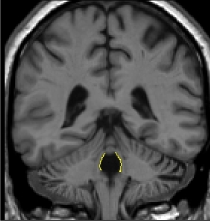

Part III – fourth ventricle in the brainstem and cerebellum

As

the 4th ventricle is surrounded by cerebellum white matter, multiple histograms

will yield the most accurate fit. Generate a histogram from a box containing

CSF of the fourth ventricle and the cerebellum white matter. The only part

of the contour that you want is that between the cerebellar white matter

and the CSF of the fourth ventricle. Now generate the rest of the outline

with the histogram method.

The box for your second histogram should contain equal amounts of CSF from

the fourth ventricle and the brainstem. The generated contour will accurately

define the border between the fourth ventricle and the brainstem.